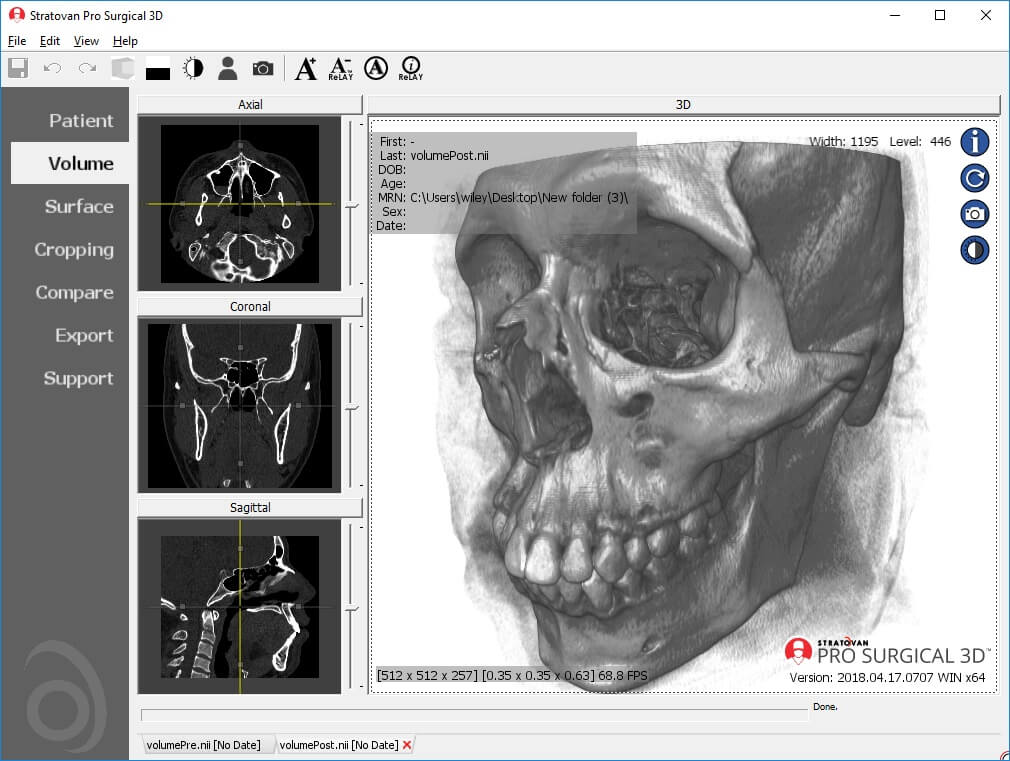

The Pro Surgical 3D application (from the Stratovan Group) is mainly targeted at surgeons, for surgical planning using their high quality 3D reconstruction feature. However, anyone can use this application to read and understand scans. It has the capacity to anonymize and de-identify patient details in scans, which is a must when the images are used in research, presentations or publications. They have an integrated customer support portal to aid in usage. The application also provides access to the Navegatium Knowledge Base—a comprehensive digital library of medical images.

Some drawbacks are that it occupies a lot of hard disk space, requires an advanced version of Windows (at least Windows 8.1 or 10) and high-speed RAM.

| 5. | Pro Surgical 3D | Windows 8.1 or higher | Not available | Y | Y | N | STL and PLY formats | 1 GB | Intel i3/ 8+ GB RAM; 1920x1080 | Freeware |